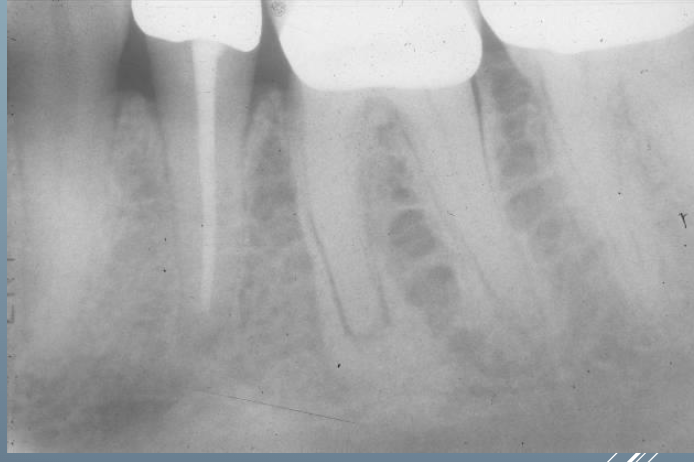

Q

What’s this?

A

HEMATOPOIETIC BONE MARROW DEFECT

FOCAL OSTEOPOROTIC BONE MARROW DEFECT